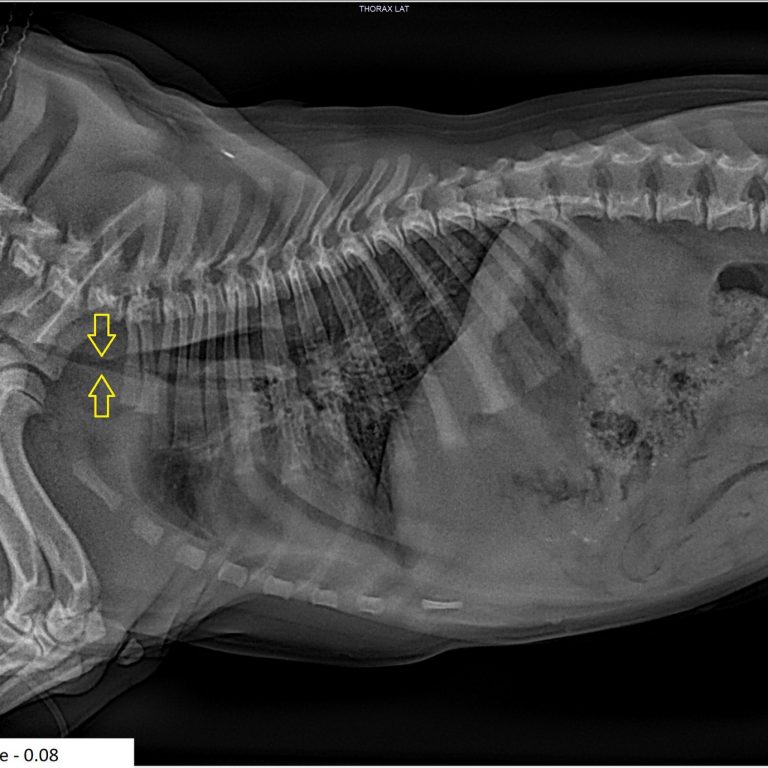

A trachea is considered hypoplastic if it’s ratio is less than 0.16. to 0.20 is a grey area and over 0.20 is excellent. Please see the examples below including Archie who has a normal width of 0.20. Compare the 3 severely hypoplastic ones pictured below.

The three cases discussed/pictured above are extreme. All puppies, all really struggling with bouts of aspiration pneumonia, and all diagnosed with extreme hypoplastic tracheas. Their measurements were 0.07 for two of them and 0.08 for one.

Winnie: 18 months later Winnie is a wonderful happy dog enjoying life as much as most! At her repeat surgery at 12 months her trachea now has a ratio of 0.12. Still terrible, but far better than 0.08, a 50% improvement as she grew.